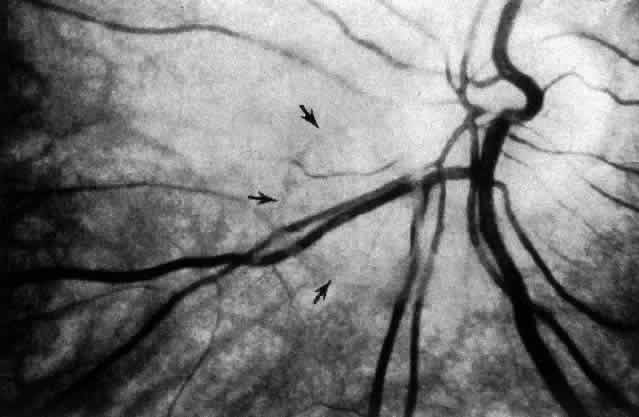

There is an unusual vitreoretinal interface overlying retinal blood vessels. Kuwabara and Cogan194 described “spider-like bodies” in the peripheral retina that coiled about blood vessels and connected with the ILL. Pedler195 found that the ILL was thin over blood vessels and hypothesized that this was due to the absence of Müller cell inner processes. Wolter196 noted the existence of pores in the ILL along blood vessels and found vitreous strands inserted where the pores were located. Mutlu and Leopold197 described that these strands extend through the ILL to branch and surround vessels in what they termed “vitreoretinovascular bands.” Such structures would explain the strong adhesion between vitreous and retinal blood vessels. This may provide a shock-absorbing function damping arterial pulsations during the cardiac cycle. However, pathologically, this structural arrangement could also account for the proliferative and hemorrhagic events associated with vitreous traction on retinal blood vessels.